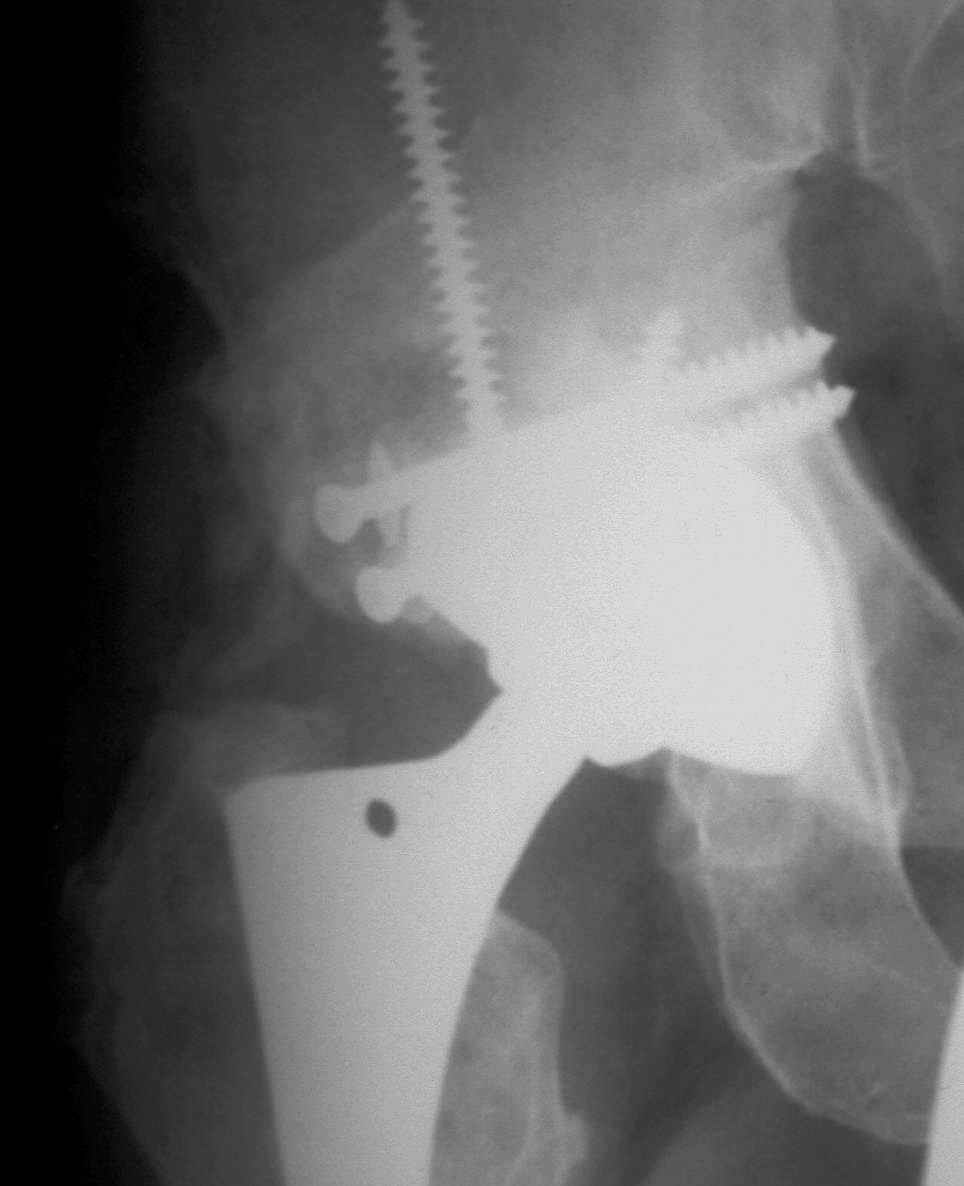

В институте совместно с фирмой Зиммер достаточно регулярно (практически ежемесячно) проводятся 2-х недельные циклы по различным вопросам эндопротезирования. Если есть возможность и желание, мы готовы поделиться с Вами нашим опытом, тем более есть что показать и что обсудить - в настоящее время ежедневно выполняется от 6 до 10 эндопротезирований коленного и тазобедренного сустава. В качестве примеров хочу показать 2 наблюдения, через 1 год и 5 лет после операции

1 год